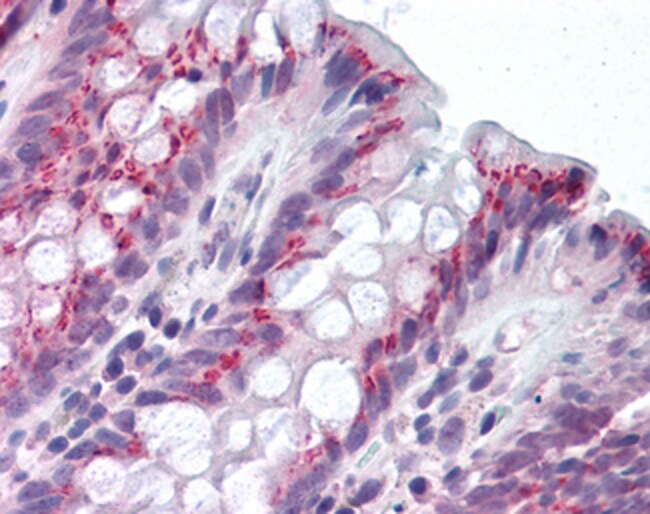

Aplicaciones Immunohistochemistry (Paraffin), Western Blot

IDO1 is an intracellular heme-containing enzyme that catalyzes the oxidative cleavage of the indole ring of several important regulatory molecules like tryptophan, serotonin, and melatonin. By doing this, IDO1 initiates the production of biologically active metabolites, commonly referred to as kynurenines. IDO1 is widely expressed in a variety of human tissues as well as in macrophages and dendritic cells (DCs). In inflammation, interferons (IFNs) act on specific receptors to trigger IDO1 induction. The production of IFN-gamma and induction of IDO1 represent important antimicrobial mechanisms. Degradation and depletion of tryptophan by IDO1 inhibits the growth of viruses, bacteria and parasites. Furthermore, IDO1 plays a complex and crucial role in immunoregulation during infection, pregnancy, autoimmunity, transplantation, and neoplasia.